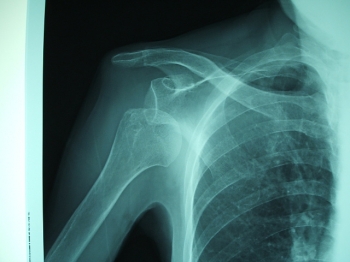

1位 肩脱臼

4位 肩鎖関節脱臼